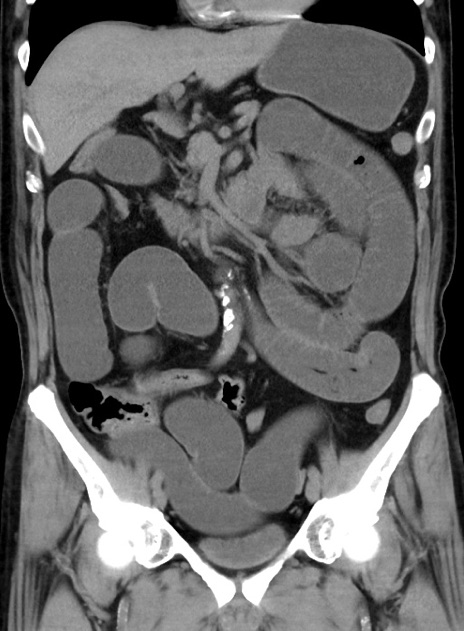

症例38(冠状断像)

【症例】70歳代 男性

【主訴】腹痛・嘔吐

【現病歴】昨晩より、嘔吐・腹痛あり。今朝になっても嘔吐あり。来院。

【既往歴】心臓バイパス手術、開腹胆摘、腸閉塞

【身体所見】BP 107/71mmHg、HR 116/min、腹部:平坦、軟、下腹部に軽度圧痛あり。反跳痛なし。

【データ】WBC 15100、CRP 0.32